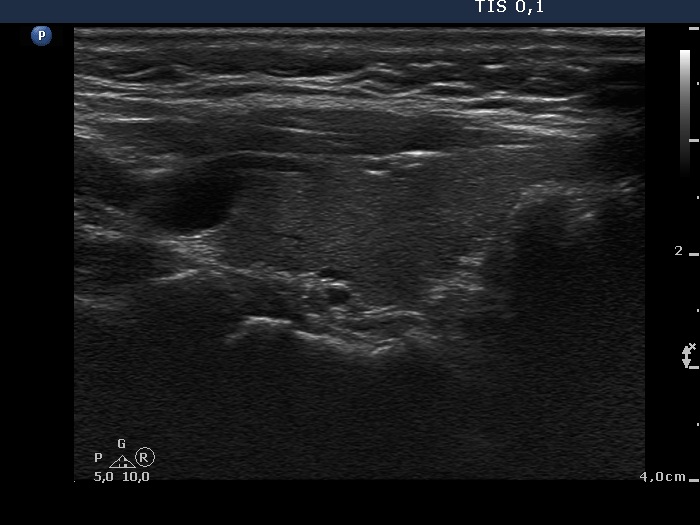

Right lobe, longitudinal scan

Left lobe, longitudinal scan. There is an intrathyroidal large vessel in the upper pole of the lobe (left in the image).